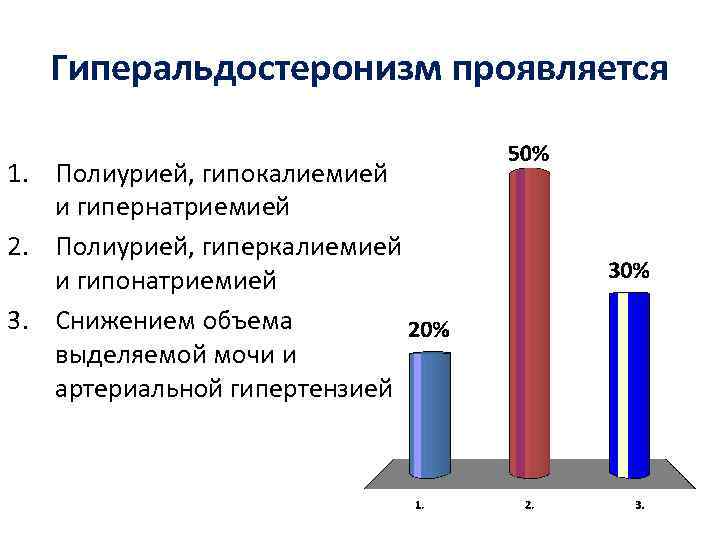

Гиперальдостеронизм проявляется 1. Полиурией, гипокалиемией и гипернатриемией 2. Полиурией, гиперкалиемией и гипонатриемией 3. Снижением объема выделяемой мочи и артериальной гипертензией

Гиперальдостеронизм проявляется 1. Полиурией, гипокалиемией и гипернатриемией 2. Полиурией, гиперкалиемией и гипонатриемией 3. Снижением объема выделяемой мочи и артериальной гипертензией